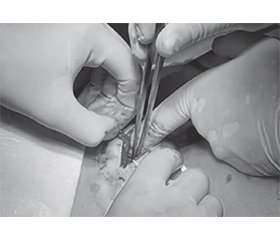

Онкологічний біль виникає у пацієнтів з онкологічними захворюваннями через ураження тканин, запалення, здавлювання нервів або наслідки лікування. Біль може значно знижувати якість життя, але сучасна медицина пропонує ефективні підходи до його контролю. Якщо полегшення болю досягається лише за рахунок високих доз опіоїдів, методом вибору є інтервенційні процедури знеболювання, такі як черезшкірні тунельні епідуральні катетери, повністю імплантовані системи для інтратекального або епідурального введення. Імплантовані порт-системи є ефективним інструментом у лікуванні онкологічного хронічного болю та забезпечують зручний і тривалий доступ до терапії. Вони дозволяють доставляти аналгетики та інші препарати безпосередньо у спинномозкову систему, мінімізуючи побічні ефекти та покращуючи якість життя пацієнтів. Імплантовані порт-системи значно підвищують якість життя пацієнтів з хронічними захворюваннями або потребою у регулярному лікуванні.

Cancer pain occurs in oncologic patients due to tissue damage, inflammation, nerve compression or the effects of treatment. Pain can significantly reduce the quality of life, but modern medicine offers effective approaches to its control. If pain relief is achieved only with high doses of opioids, the method of choice is interventional pain management procedures such as tunneled epidural catheters, fully implanted systems for intrathecal or epidural administration. Implantable port systems are an effective tool in the treatment of chronic cancer pain and provide convenient and long-term access to therapy. They allow the delivery of analgesics and other drugs directly to the spinal cord, minimizing side effects and improving the quality of life of patients. Implantable port systems significantly improve the quality of life of patients with chronic diseases or the need for regular treatment.